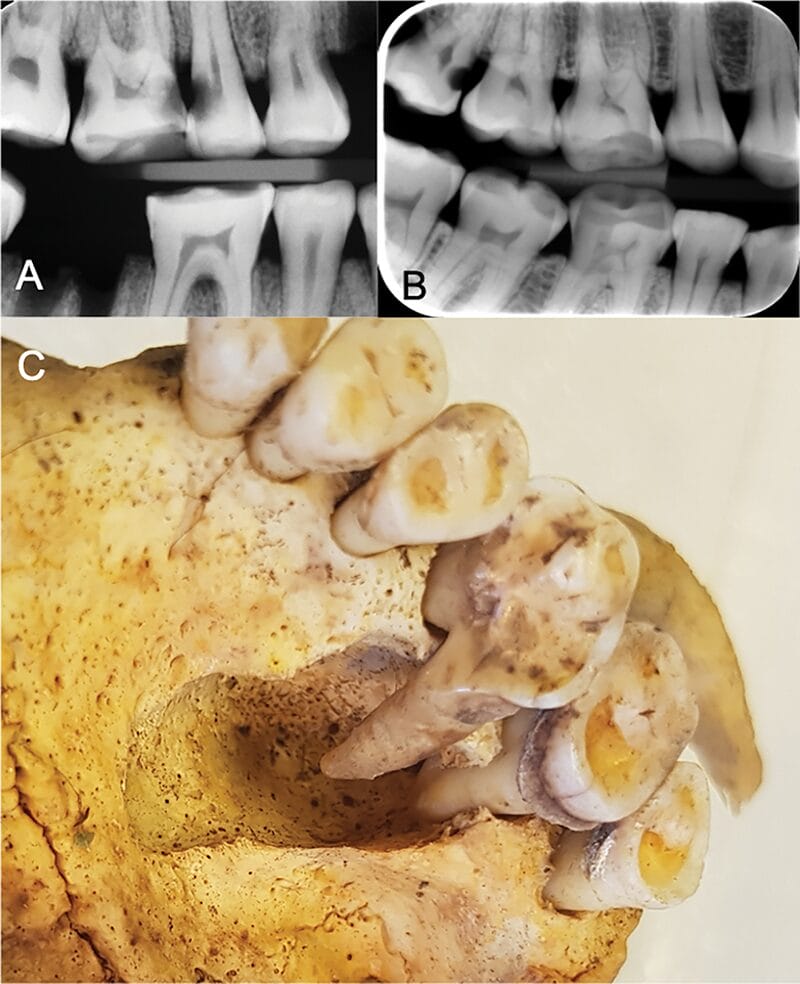

A) Signs of habitual wear of the central incisors, B) Signs of tooth picking in the mandibular incisors, C) Signs of modification with the opening of the pulpal chamber of a mandibular molar, D) Filed anterior teeth, and E) Modified central incisor with fistulated apical infection.

The study also uncovered interesting examples of Viking efforts to maintain their dental health. “There were several signs that the Vikings had modified their teeth, including evidence of using toothpicks, filing front teeth, and even dental treatment of teeth with infections,” explains Carolina Bertilsson, a dentist and Associate Researcher, who was the study’s first-named and corresponding author.2 Notably, the areas of teeth with abrasion marks from using toothpicks showed no carious lesions. The filed anterior teeth found among the Viking remains hint at the possibility of these modifications serving as identity markers.1

One particularly fascinating find was molars with filed holes extending from the tooth’s crown into the pulp. This adaptation likely alleviated severe toothaches caused by infections, suggesting sophistication in dental procedures. Remarkably, this procedure bears a resemblance to modern dental treatments.1